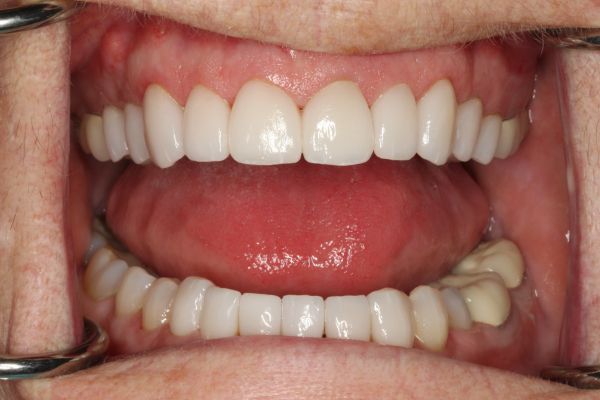

Crowns on upper front teeth 6-11 and lower front teeth 22-27 Crowns on the molars and bicuspids on the upper right and lower right. 3/4/5/28/29/30.

You’re never too old to put your best smile forward! For this patient, a lifetime of multiple failed bridges and discomfort was part of aging. Complicating matters, like so many patients in need of significant dental work, our patient was afraid of the dentist. Experiences early on in life had taught her to fear the dentist and that a trip to the dentist was associated with pain. As a result, she was self-conscious about her teeth and her appearance. Her teeth had darkened and become stained—symptoms that only exacerbated the crookedness of her smile. With help from sedation dentistry, we provided the life-changing treatment that our patient so desperately wanted. After several new dental implants, laser gum surgery to address underlying gum disease and new pearly white veneers we straightened her teeth and gave her the smile she’d always wanted. Today, our patient is all smiles and wonders why she deferred treatment for so long!